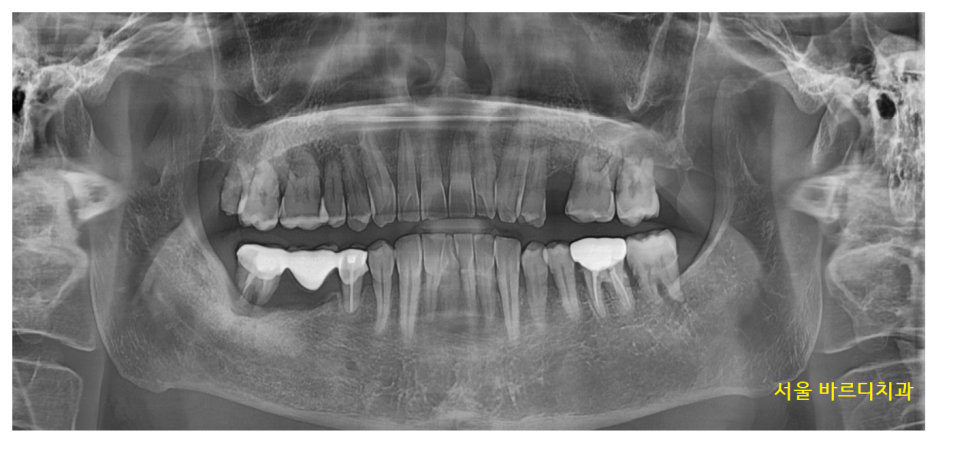

강일역 치과를 방문해 주신 환자분 사진입니다.

아... 큰 사진에서도

문제 치아를 바로 발견했는데요.

23.02.08

오래전 브릿지로 씌워둔 치아가

수명을 다했네요.

잇몸뼈가 많이 녹아서

뿌리 끝부분만 붙잡고 있는 게 보이시죠~?

보철물 아래쪽으로 음식물도 끼고

불편하셨겠어요.